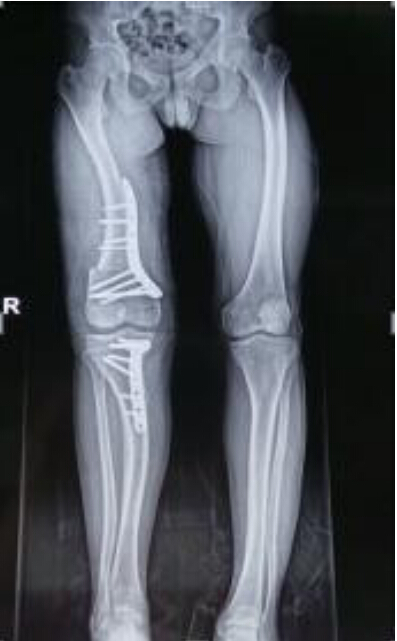

截骨導板輔助完成膝關節內外矯形截骨手術

膝關節內外矯形截骨病例,傳統的手術矯形截骨術都是通過醫生的經驗及術前在X線片上的測量得到需要截骨的多少,同時手術過程中會由于醫生的經驗不同及機械性誤差而導致術后截骨的精確度不高。現在我們通過影像數據重建患者病理模型,然后打印出患者病理骨骼模型。同時運用設計軟件,根據膝關節的解剖關系進行矯形截骨導板的設計,并打印出截骨導板。然后經過消毒后用截骨導板進行手術操作,實現精確截骨,恢復下肢力線,最終使得恢復正常力線實現矯正畸形。該項技術克服了患者骨骼畸形行常截骨矯形術依靠醫生手術經驗及機械性誤差導致的截骨不精準、手術時間長等缺點。依靠數字化技術大大提高手術精準度及質量,減少手術時間,降低了手術風險